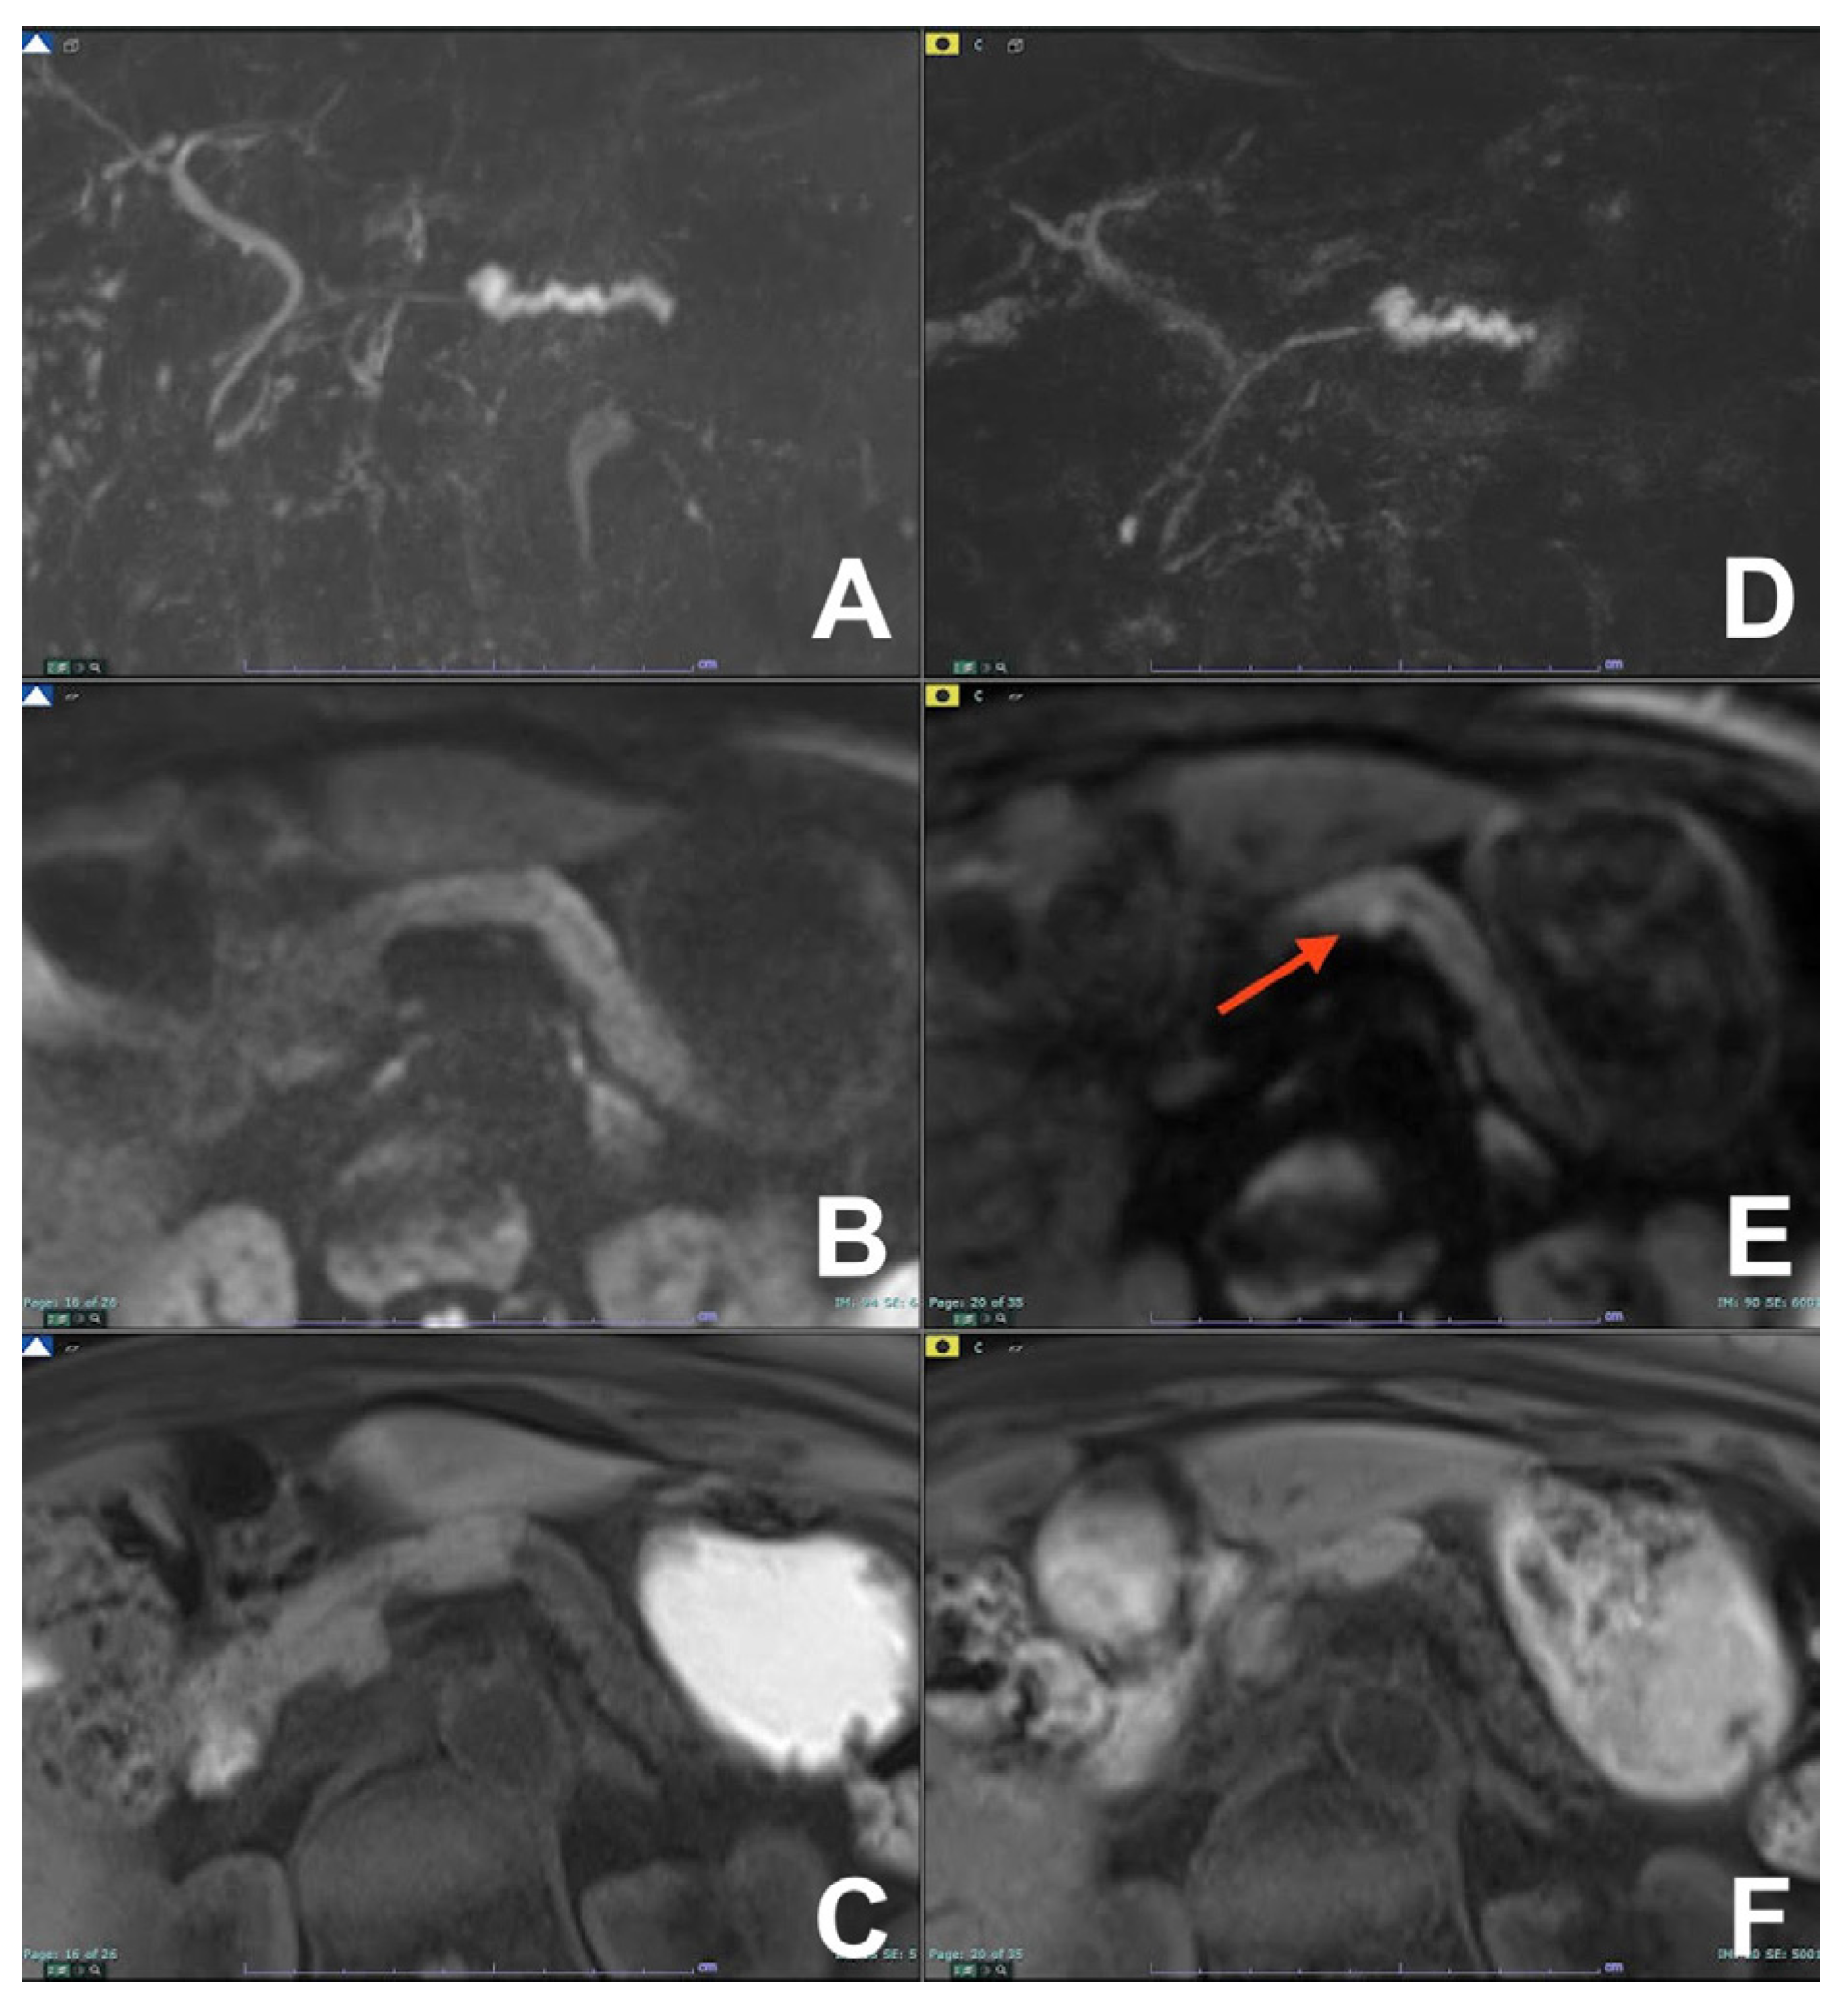

| Differential diagnosis pancreatic cancer (PC) from mass forming pancreatitis (e.g., paraduodenal pancreatitis-PDP, autoimmune pancreatitis-AIP) | HASTE T2 | AXIAL | -- | Anatomy and liquids analysis |

| Indications: The use of multiparametric imaging (DWI, contrast enhanced) allows one to differentiate with substantial accuracy a mass forming pancreatis from a pancreatic carcinoma. | HASTE T2 | CORONAL | -- | Anatomy and liquids analysis |

| GRE T1 FS | AXIAL | -- | Pancreatic parenchima assessment | |

| DWI b 0–50–400–800 | AXIAL | -- | Restricted diffusion most likely to be PC or AIP | |

| GRE T1 3D DYNAMIC | AXIAL | Pre- 25″–70″–180″ | PC is most likely hypovascular; mass forming pancreatitis usually shows delayed homogeneous enhancement | |

| MRCP 3D/2D | OBLIQUE CORONAL | Anatomy of wirsung duct | ||

| MRCP 2D with secretin | OBLIQUE CORONAL | For the differential diagnosis of pancreatic duct stenosis (“duct penetrating sign”) | ||